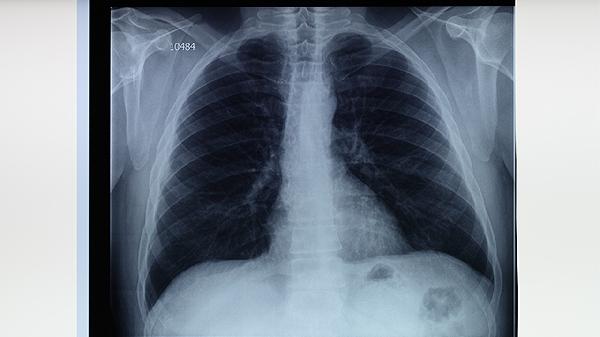

肺结核患者除规范用药外,需保持充足营养摄入优质蛋白和维生素,适当进行呼吸功能锻炼。居住环境应通风良好,避免密切接触婴幼儿及免疫力低下人群。严格遵医嘱完成6-9个月全程治疗,不可自行停药,定期复查胸部影像学和痰菌检查。出现药物不良反应应及时就医调整方案,耐药结核病患者需根据药敏试验结果选择二线药物。